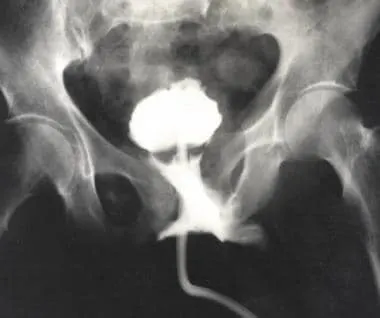

요도손상의 가장 초기 Standard evaluation은 바로 역행성요도조영술(Retrograde urethrography)이다.

"Retrograde urethrography is the standard in the early evaluation of a male urethral injury"

요도구에 조영제를 섞은 N/S 등을 주입하면서 영상을 촬영하여 조영제가 Urethra에서 방광까지 잘 통과하는지, 아니면 Urethra 밖으로 누출이 있는지를 확인해야 한다. (아래 그림 참조)

출처: https://emedicine.medscape.com/article/451797-workup?form=fpf

여기서 방광도 어느정도 채워지면서 Urethra 밖으로도 누출이 있으면 Incomplete rupture, 방광도 안채워지고 요도밖으로 다량의 누출이 있으면 Complete rupture라고 판단하게 된다.

아울러 이 검사를 통해 어디서 누출되는지를 확인하여 전부요도손상인지 후부요도손상인지도 확인하는 것이 좋다.